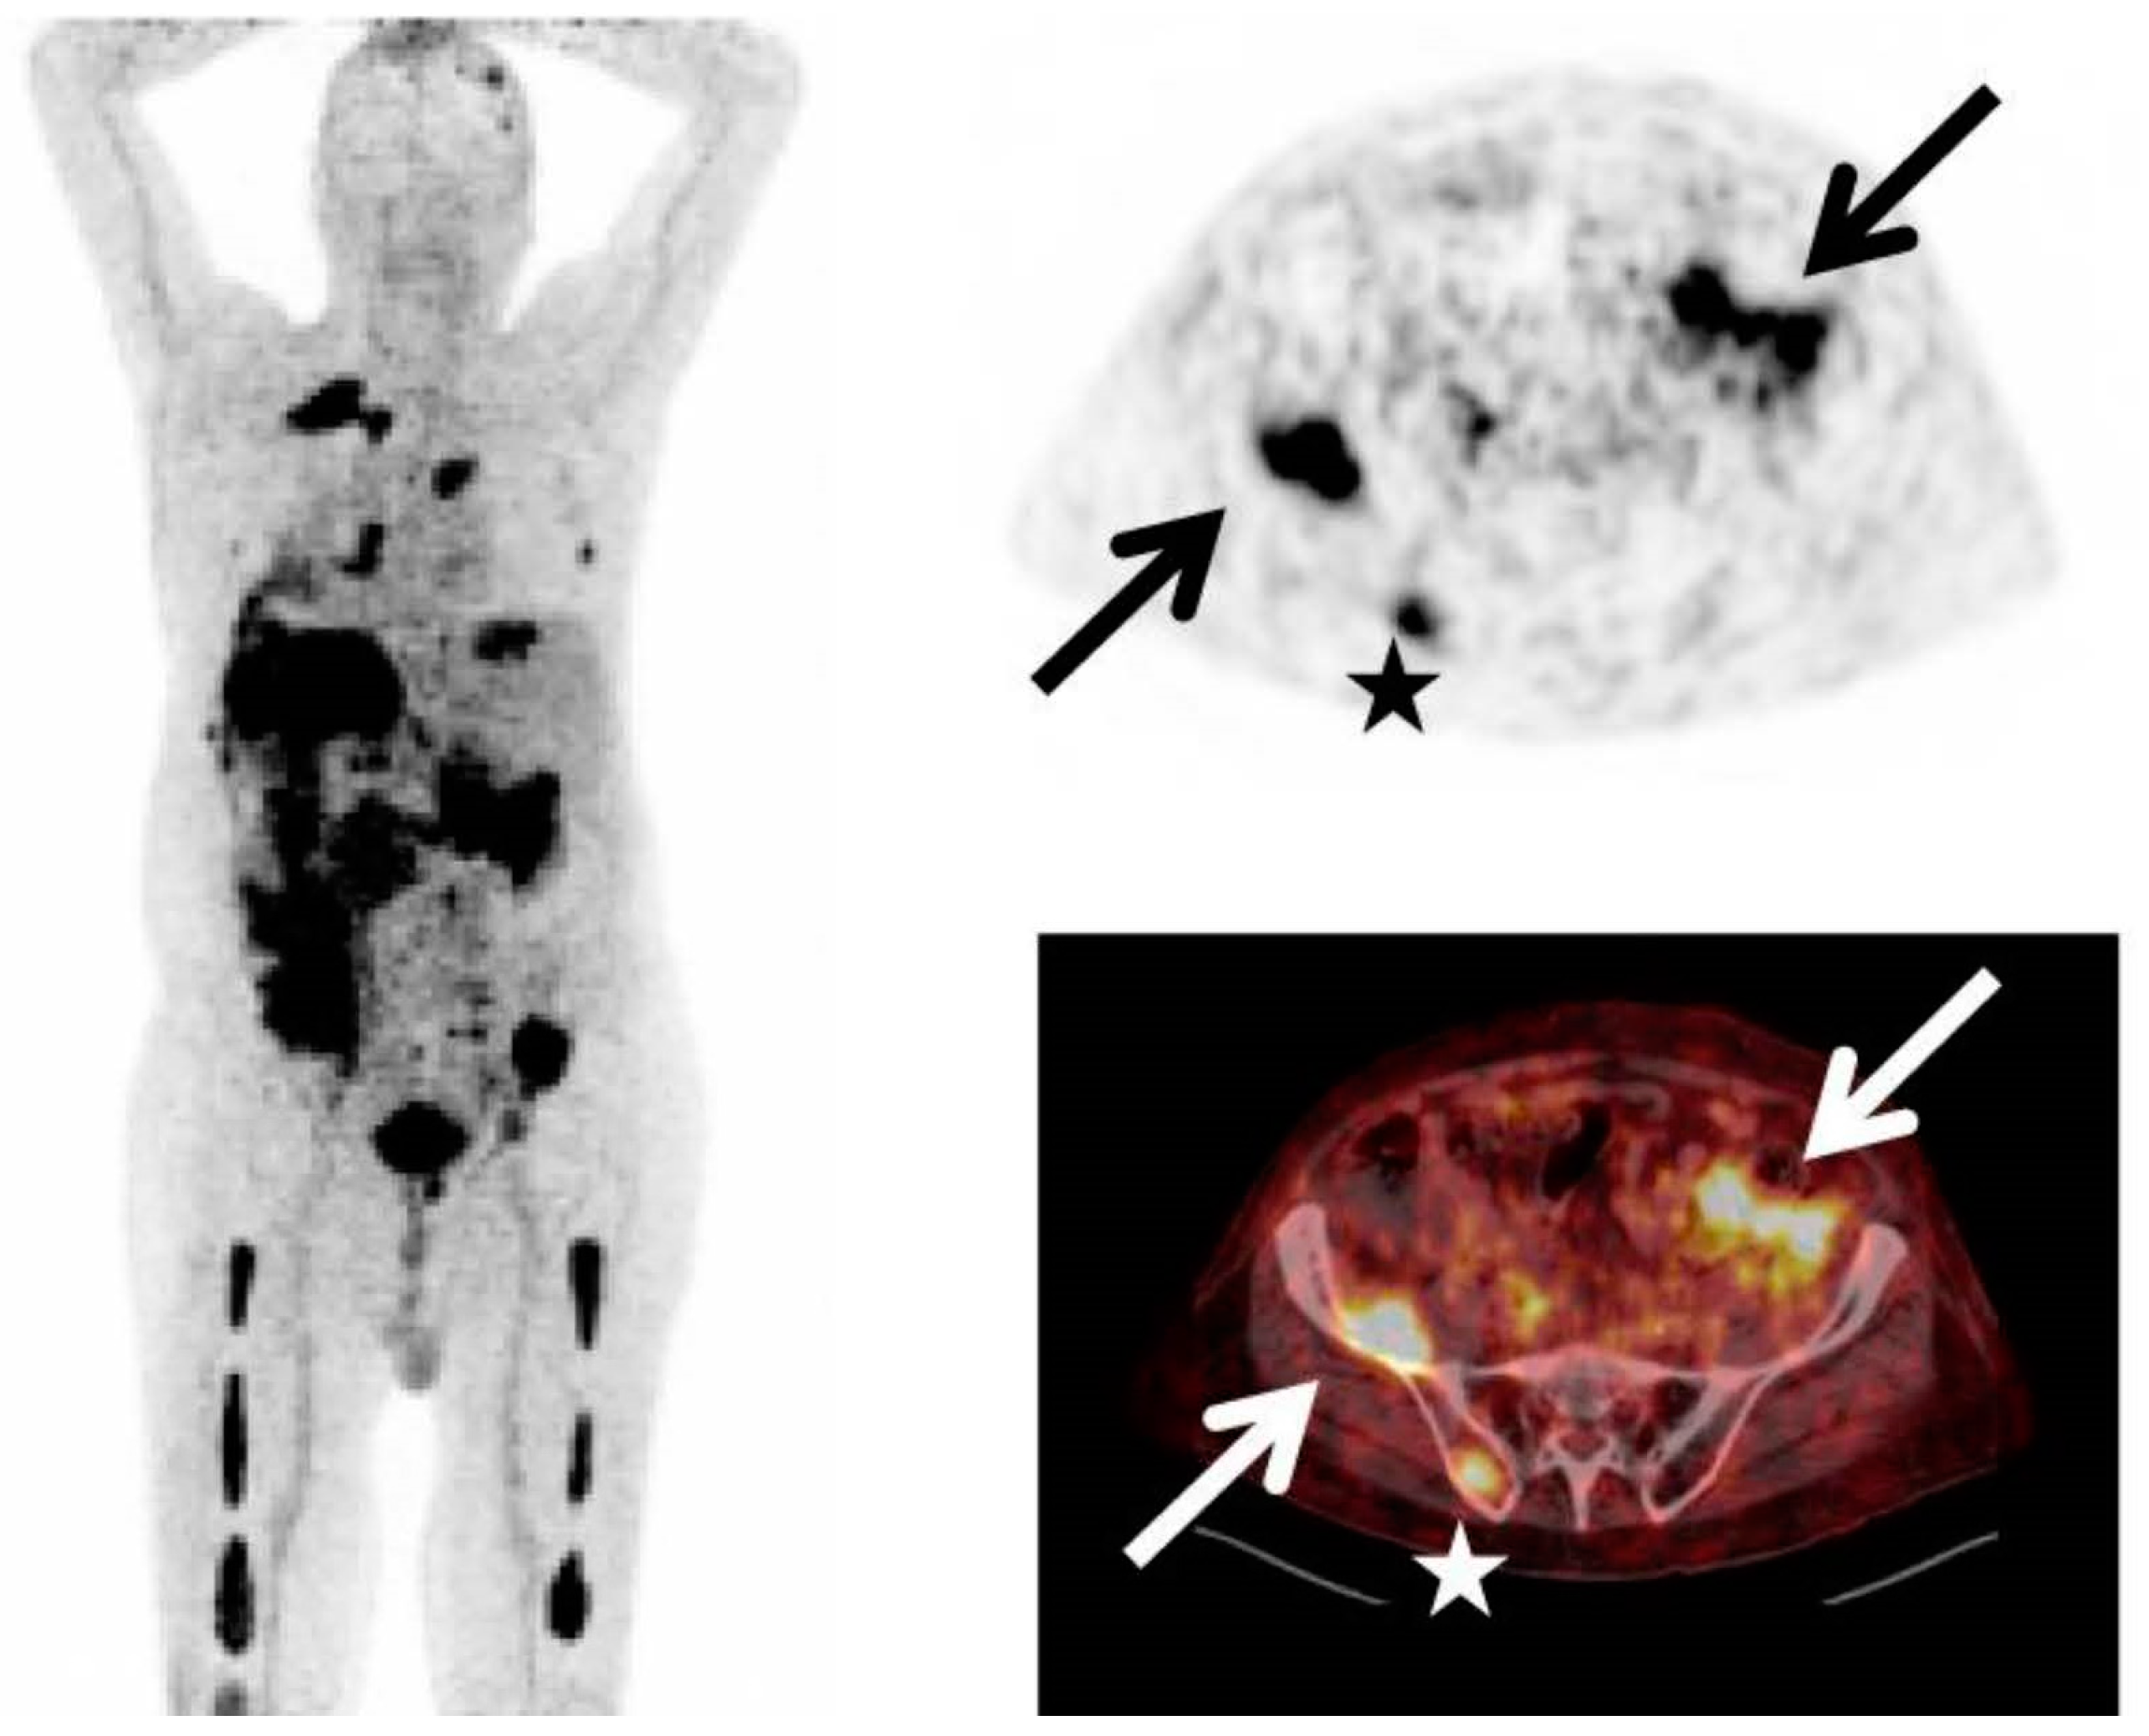

Figure 3.

This figure demonstrates the high sensitivity of [18F]FDG in detecting active MM lesions. The images present [18F]FDG PET (left) and Na[18F]F scan (right) of a 60-year-old man diagnosed with MM. The whole-body [18F]FDG PET scan reveals numerous active lesions in the skeleton and extramedullary sites (A). The whole-body Na[18F]F PET scan did not identify most of the lesions detected by [18F]FDG PET (B). The image was sourced from PMID: 31084774 (Figure 2), and permission was granted for its use.

Fractures, which impact 60–80% of myeloma patients, represent a notable adverse consequence of myeloma bone disease. While [18F]FDG can reveal fractures to a certain degree, numerous studies have demonstrated that a bone-seeking PET radiotracer, 18F-sodium fluoride (Na[18F]F), is more effective for this specific purpose [38] (Figure 7). On the other hand, most comparative studies showed that [18F]FDG is superior to Na[18F]F in identifying osteolytic lesions [38] (Figure 3). This outcome is anticipated due to the fact that Na[18F]F reflects osteoblastic activity, whereas localized myeloma lesions predominantly involve heightened osteoclast activity [38].